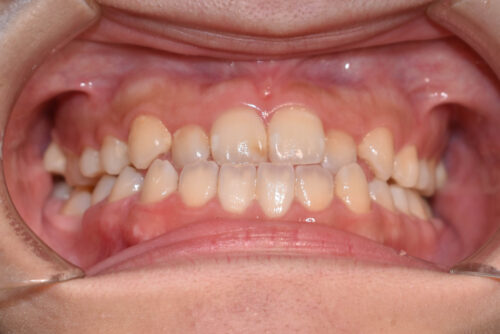

初診時年齢 28歳 女性

歯のでこぼこ(叢生)

下顎右側第一大臼歯欠損(歯をぬいた)

歯のがたつき (叢生)

と

受け口が認められました。

本症例も

下顎右側第一大臼歯欠損

上下とも歯が唇側に傾斜し

下の歯が上の歯よりも外にでている 受け口の状態でした。

ワイヤー8か月後です。